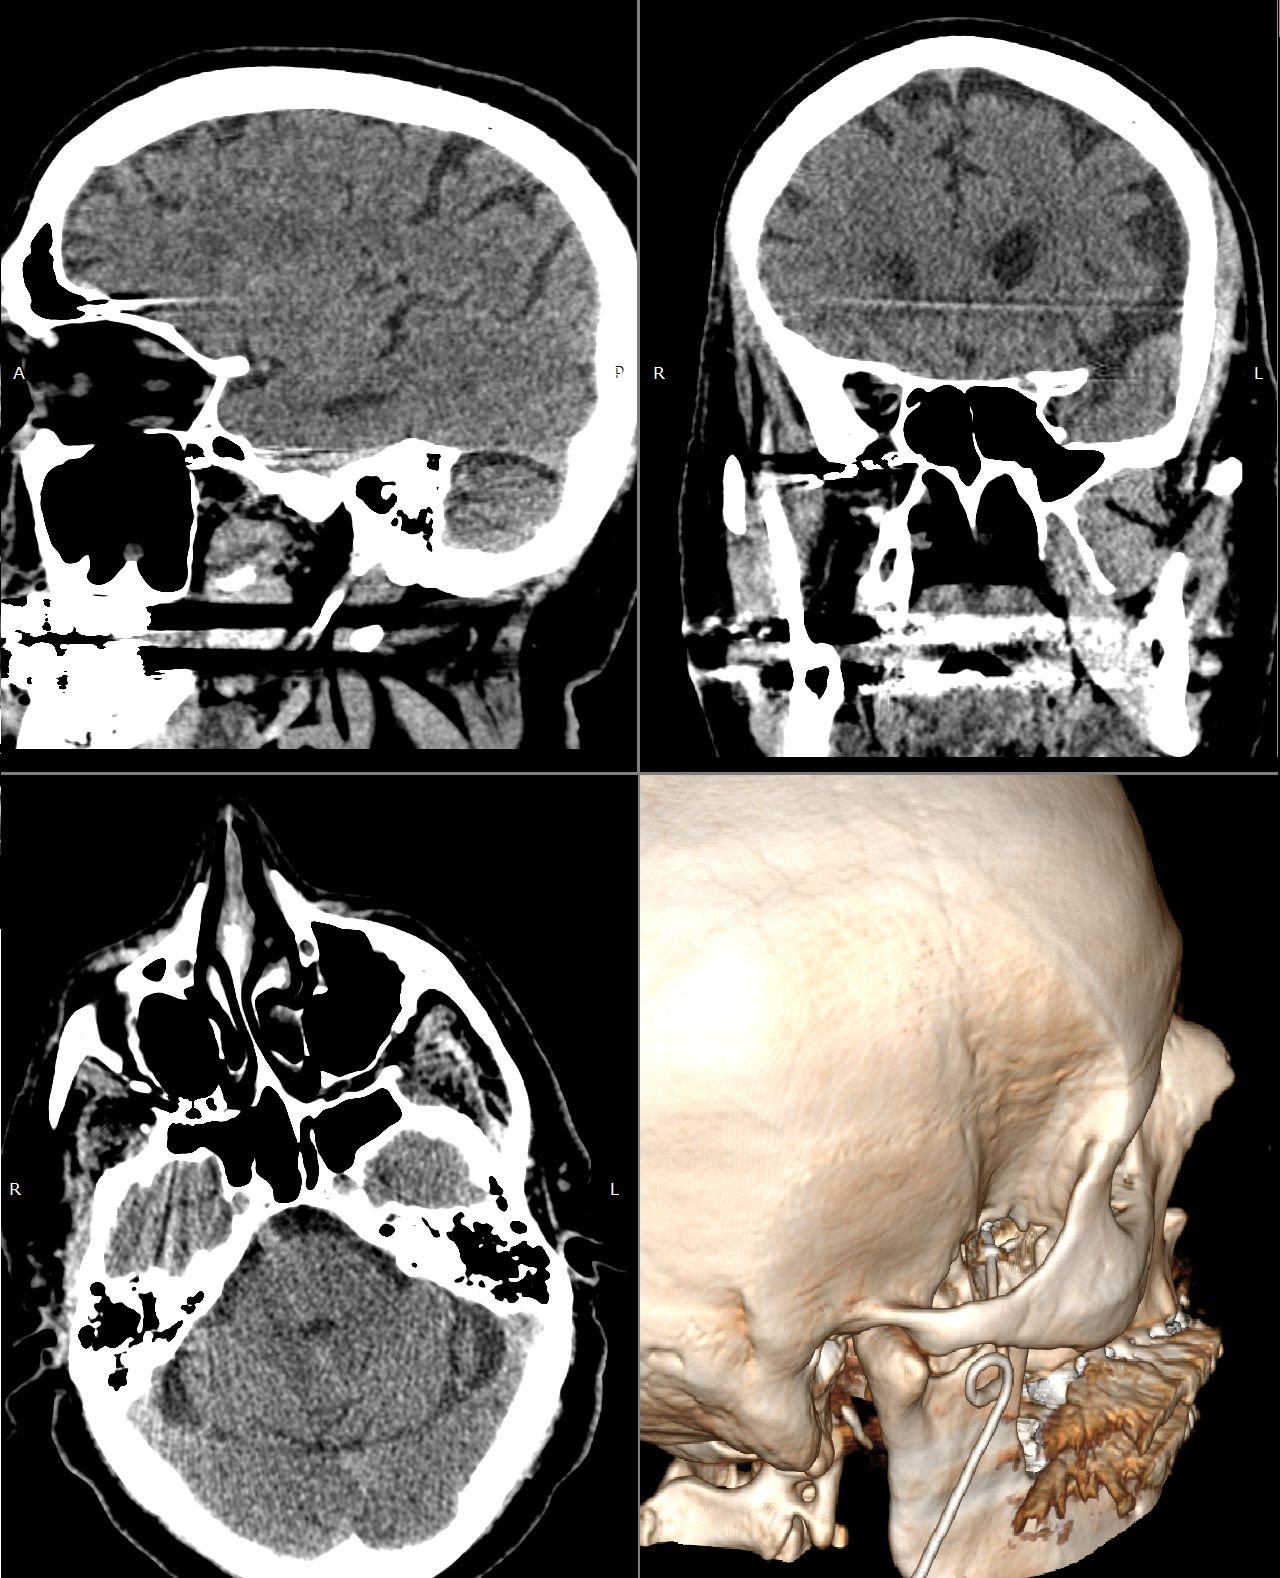

Перед выполнением вмешательства каждому пациенту проводилось предоперационное КТ-сканирование соответствующей анатомической зоны с предварительной установкой рентгеноконтрастных ориентиров (fiducial markers). При подготовке к процедурам сакральной нейростимуляции (SNRS) выполнялась КТ пояснично-крестцового отдела позвоночника, а четыре метки устанавливали в ромбовидной конфигурации в проекции поясничной области (Рисунок 1).

В случае операций по стимуляции крылонёбного ганглия (SPGS) проводилось КТ головы; при этом от применения fiducial-меток отказались, поскольку для регистрации использовали стабильные и чётко определяемые наружные анатомические ориентиры — такие как кончик носа, латеральный край орбиты и глабелла.

Рисунок 1. Расположение Fiducial-меток для SNRS на пациенте и по 3D-КТ.

При выполнении данной операции применение навигации с дополненной реальностью оказалось даже более результативным. Точное следование заранее рассчитанной траектории введения инструмента (рис. 6) обеспечило оптимальное расположение электрода в крылонёбной ямке, что впоследствии сопровождалось выраженным положительным клиническим результатом. Корректность положения стимуляционной иглы была подтверждена интраоперационной флюороскопией, после чего произведена имплантация четырёхконтактного электрода. Финальная позиция системы была дополнительно верифицирована по данным послеоперационной компьютерной томографии (рисунок 7).

Рисунок 7. КТ- контроль положения электрода для SPGS. Видно, как электрод располагается полностью в крыловидно-нёбной ямке справа.